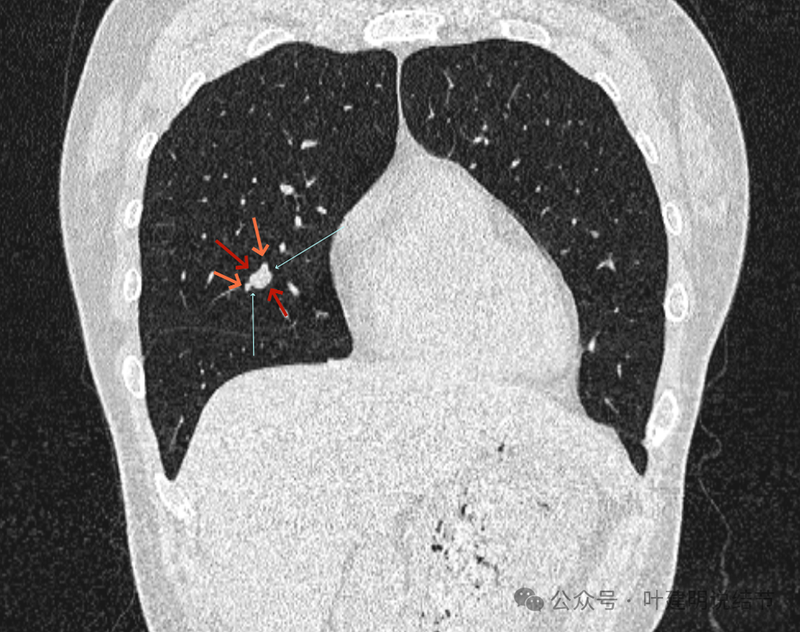

再看冠状位影像:

血管与病灶的关系,两者密度稍不同,天蓝色细箭头所指是分界线。

血管征明显。

血管围着病灶,病灶有膨胀性,表面欠平滑。

不而有膨胀性,血管贴着并被压迫。

边缘欠平滑,邻近血管间隙欠清晰。

血管贴着,结节膨胀。

也示血管与病灶的关系。

结节实性。

纵隔窗这个角度明显见到蓝色箭头所指的血管被病灶侵蚀,而且血管与病灶密度的不同。